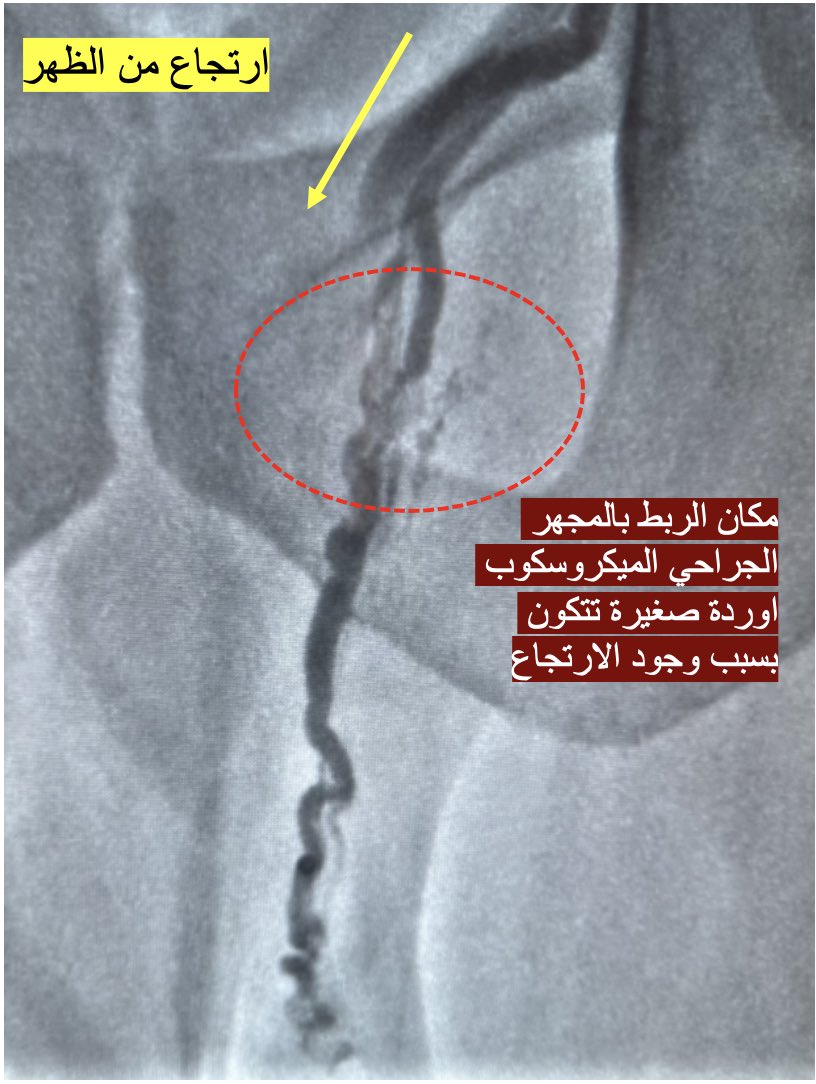

١٣- النقطة الأخرى وهي الأهم: عدم علاج الارتجاع من الوريد الخصوي يؤدي مع الوقت إلى ظهور أوردة أخرى (تماماً مثل علاج دوالي الفخذ دون علاج الوريد الصافن). وهذا أهم اسباب عودة الدوالي المتأخر بعد الجراحة المجهرية.

١٤- لكن ، لماذا لا يتم جراحياً ربط الوريد الخصوي كذلك؟ لأن الوريد الخصوي يمتد لأعلى الظهر. ويخرج الى الخصية عن طريق القناة الاربية. تمزيق الأغشية بالمنطقة الأربية قد يؤدي الى حدوث مشكلة اكبر وهي الفتق. ماذا عن عملية منظار البطن؟ هذه احدى الطرق التي قام بعض جراحين المسالك من الغرب باستخدامها لربط الوريد الخصوي. لاحظ وجود الشعيرات الدموية بالأغشية (سهم).